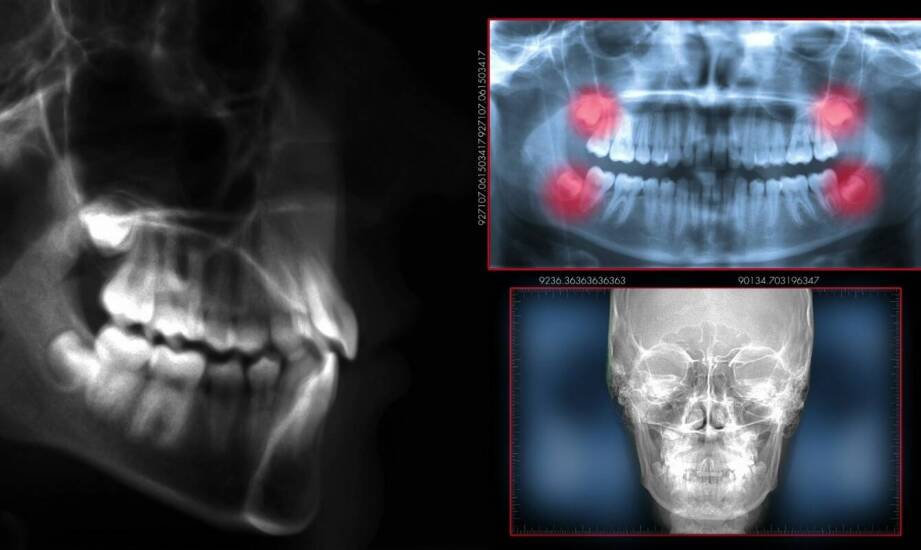

Wykonywanie zdjęć rentgenowskich zębów wymaga zastosowania nowoczesnych technologii, które zwiększają dokładność i jakość obrazów. W stomatologii stosowane są różne techniki RTG, takie jak zdjęcia punktowe i panoramiczne. Obie metody mają swoje zalety, a ich wybór zależy od potrzeb pacjentów oraz problemu stomatologicznego. Innowacje w tej dziedzinie przyczyniają się do lepszego zrozumienia problematyki stomatologicznej, co pozwala na precyzyjne diagnozowanie i skuteczne leczenie. Dzięki wieloletniemu doświadczeniu specjalistów oraz nowoczesnym technologiom, w tym rtg zęba w Gorlicach, można liczyć na niezawodność i precyzję wyników badań rentgenowskich.